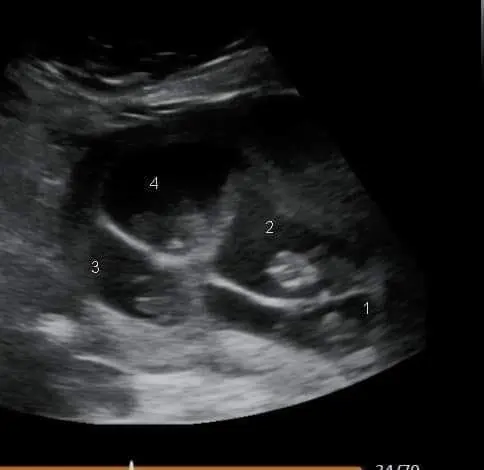

Детская медсестра из Фелпса, штат Нью-Йорк, 34-летняя Карисса Ванкамп-Смит и её 32-летний муж Диллон узнали о том, что ждут ребёнка, в декабре 2021 года. После трёх выкидышей и потери младенца они были потрясены, когда во время частного сканирования на сроке шесть недель УЗИ показало, что Ванкамп-Смит носит четверню.

«Сразу же на экране появились два ребёнка, потом третий, а потом и четвёртый, — говорит она. — Мы потеряли дар речи».

«Мы даже не подозревали, что они идентичны, пока врач не заметил их сходство и единую плаценту. Они были здоровы, но остались в больнице из-за недоношенности».